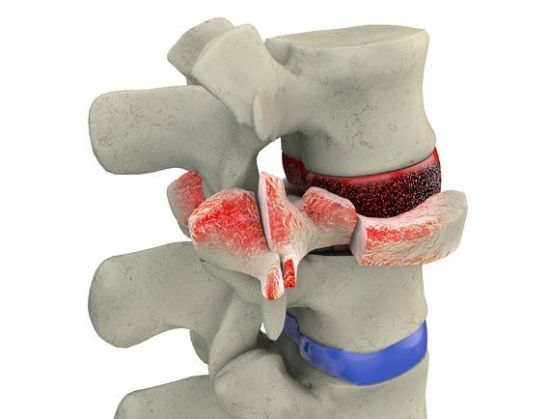

Хоть опухоль является доброкачественной, она может вести себя очень агрессивно, и в какой-то момент начинает увеличиваться в размерах, доставляя дискомфорт и болезненные ощущения. Начав расти, она может достичь таких размеров, что сожмет спинной мозг, передавит нервные окончания и даже спровоцирует надлом одного из позвонков.

- переломы позвоночного столба (в месте роста сосудистой опухоли);

Физиотерапевтические аппараты

Чрезмерный рост гемангиомы ведёт за собой нарушения работы внутренних органов. Также в результате развития опухоли у позвонка может снижаться прочность, поскольку его целостная структура разрушена. Это приводит к тому, что в дальнейшем будет достаточно всего лишь небольшой нагрузки для того, чтобы однажды случился перелом тела позвонка.

Нарушение строения позвонка в любой момент способно приобрести критическую форму, когда даже незначительная травма или физическая нагрузка способна привести к перелому позвоночника. Иногда активный рост гемангиолипомы способствует раскалыванию кости, придавливая обломками нервные волокна.